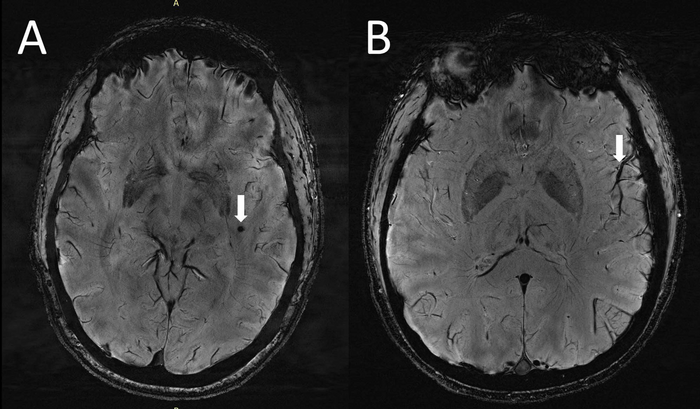

Ennek köszönhető, hogy először sikerült megfigyelni, hogy a krónikus migrénben és epizodikus, aura nélküli migrénben szenvedőknél jelentős változások következnek be a centrum semiovale nevű agyi régió perivaszkuláris tereiben. A 7T MRI egyébként annyira új technológia, hogy a londoni King's College is tavaly készített ilyen felvételt először. A T betű a Teslára utal, ami ebben az esetben a mágneses indukció mértékegysége – a technológia lényege ugyanis, hogy az erősebb mágnesek segítségével képes jóval nagyobb felbontású képeket készíteni az eddigi MRI készülékeknél, így ezeken már az egészen finom elváltozások is érzékelhetőek.

A vizsgálatban 10 krónikus migrénben szenvedő, 10 aura nélküli epizodikus migrénben szenvedő beteg, valamint öt főnyi korosztályos egészséges kontrollcsoport vett részt – minden beteg 25 és 60 év közötti volt. A statisztikai elemzés kimutatta, hogy a centrum semiovale-ban a megnagyobbodott perivaszkuláris terek száma szignifikánsan magasabb volt a migrénes betegekben, mint az egészséges kontroll csoport tagjai esetében. A kutatók azt feltételezik, hogy a migrénes betegek perivaszkuláris tereinek jelentős különbségei az egészséges csoporthoz képest az agyi glimphaticus rendszer (tehát a korábban említett „tisztító rendszer”) zavarára utalhat. Mindennek bizonyításához további, kiterjedtebb vizsgálatokra van azonban szükség.